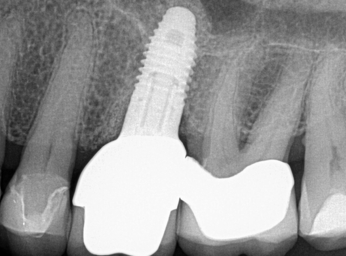

Peri-implantitis is defined as a bacterial plaque-associated pathological condition related to oral biofilm occurring in tissues around dental implants, characterized by inflammation in the peri-implant mucosa and subsequent progressive loss of surrounding bone1-8(Figure 1 and Figure 2). Food impaction is a contributing but not a primary factor in the disease process.

(1.) Peri-implantitis bone loss.

Figure 1

(2.) Peri-implantitis bone loss.

Figure 2